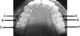

Dental enamel hypoplasia

Enamel hypoplasia is a defect of the teeth in which the enamel is deficient in amount, caused by defective enamel matrix formation. Defects are commonly split into one of four categories, pit-form, plane-form, linear-form, and localised enamel hypoplasia. [Source: Wikipedia ]